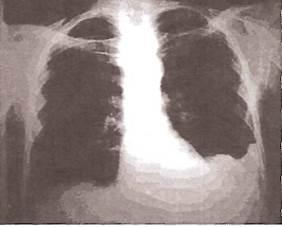

Рентгенологическое исследование

Рентгенологическое исследование для диагностики плеврального выпота имеет решающее значение. При фибринозном (сухом) плеврите

также могут быть получены важные, хотя и неспецифические данные, позволяющие с определенной степенью вероятности подтвердить наличие воспалительного процесса в листках плевры.

К рентгенологическим признакам сухого плеврита относятся:

- высокое стояние купола диафрагмы на стороне поражения;

- ограничение подвижности купола диафрагмы и нижних границ легкого при глубоком дыхании (выявляется при рентгеноскопии органов грудной клетки);

- снижение прозрачности легочного поля над диафрагмой и в области реберно-диафрагмального синуса (рис. 21).

Рис. 21.

Высокое стояние купола диафрагмы при фибринозном (сухом) плеврите.

Заметно небольшое снижение прозрачности легочного поля над куполом диафрагмы.

При выпотном плеврите

наиболее ранним рентгенологическим признаком скопления жидкости в плевральной полости является сглаживание (облитерация) острого реберно-диафрагмального угла с вогнутой верхней границей уровня жидкости (R.H. Ingram, 1995; рис. 22).

Рис. 22

. Сглаживание острого реберно-диафрагмального угла при небольшом объеме плеврального выпота.

По мере нарастания объема экссудата на рентгенограммах начинает определяться однородное затемнение, которое прилежит к наружному краю грудной клетки и диафрагме. Верхняя граница затемнения чаще располагается косо — сверху вниз и снаружи кнутри (рис. 23). При перемене положения тела затемнение и его верхняя граница меняют свою форму и расположение в связи с перемещением жидкости (рис. 24).

При скоплении в плевральной полости большого количества экссудата в нижнебоковых отделах легочного поля появляется значительных размеров треугольная тень с косой верхней внутренней границей. При этом купол диафрагмы уплощается, а средостение смещается в здоровую сторону (рис. 25).

Рис. 23.

Рентгенограмма легких при экссудативном плеврите и умеренном количестве плевральной жидкости.

Заметно интенсивное затемнение нижнего легочного поля слева, небольшое увеличение левой половины грудной клетки. Смещение средостения отсутствует

Рис. 25.

Рентгенограмма легких больного с правосторонним экссудативным плевритом